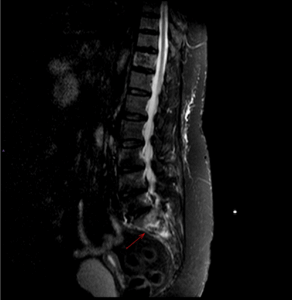

Figure 4: MRI showing sacral insufficiency fracture on background of osteoporosis and parathyroidectomy

Figure 5: MRI showing sacral insufficiency fracture on background of osteoporosis and parathyroidectomy

Figure 6: MRI showing sacral insufficiency fracture on background of osteoporosis and parathyroidectomy